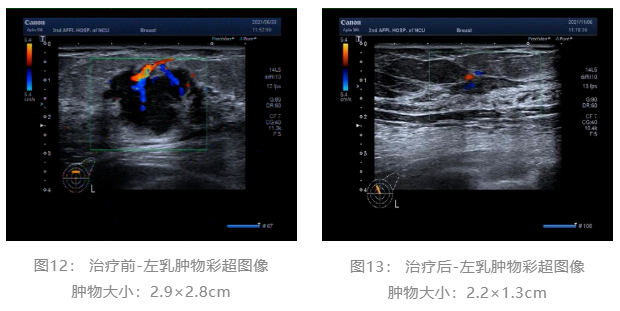

乳腺彩超: